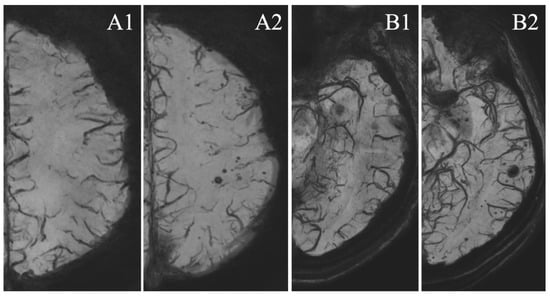

| Mean number of MSA | 8.76 [5.76; 11.76] | 0.78 [0.32; 1.25] | <0.001 | ||

| 3.77 [2.09; 5.45] | 7.78 [3.10; 12.46] | 0.022 | |||

| Appearance of MSA | 36 (78.26%) | 18 (21.74%) | <0.001 | ||

| 19 (82.61%) | 17 (73.91%) | 0.722 | |||